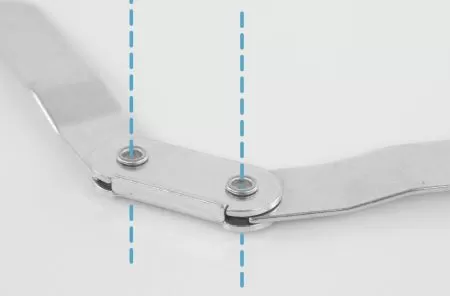

- БОКОВЫЕ МЕТАЛЛИЧЕСКИЕ РЕБРА ЖЕСТКОСТИ С ПОЛИЦЕНТРИЧЕСКИМ ШАРНИРОМ

- Обеспечивают латерально-медиальную стабилизацию и разгрузку коленного сустава, повышают стабильность и снимают боль в коленном суставе

- Обеспечивают функциональную динамику и дополнительную внешнюю поддержку сустава

- Помогают уменьшить объём движений и предотвращает патологические движения в коленном суставе

- В полностью развернутом положении ребра жесткости имеют угол 170°, это обеспечивает физиологически правильное положение, что предотвращает переразгибание коленного сустава

- Ребра жесткости малообъемные, что делает ортез практически

- Движение шарниров максимально приближено к естественной физиологии движений коленного сустава, что позволяет использовать ортез длительное время на различных этапах реабилитации, восстанавливая правильный двигательный стереотип

- МЕТАЛЛИЧЕСКИЕ РЕБРА ЖЕСТКОСТИ С ПОЛИЦЕНТРИЧЕСКИМ ШАРНИРОМ:

- Шины съемные, благодаря чему ортез можно использовать для поэтапной реабилитации

- Шины выполнены из аллюминия, поэтому их можно адаптировать под анатомические особенности ноги, при необходимости

- Шина надежно фиксируется в «кармане» за счет клапана с застежкой micro velcro